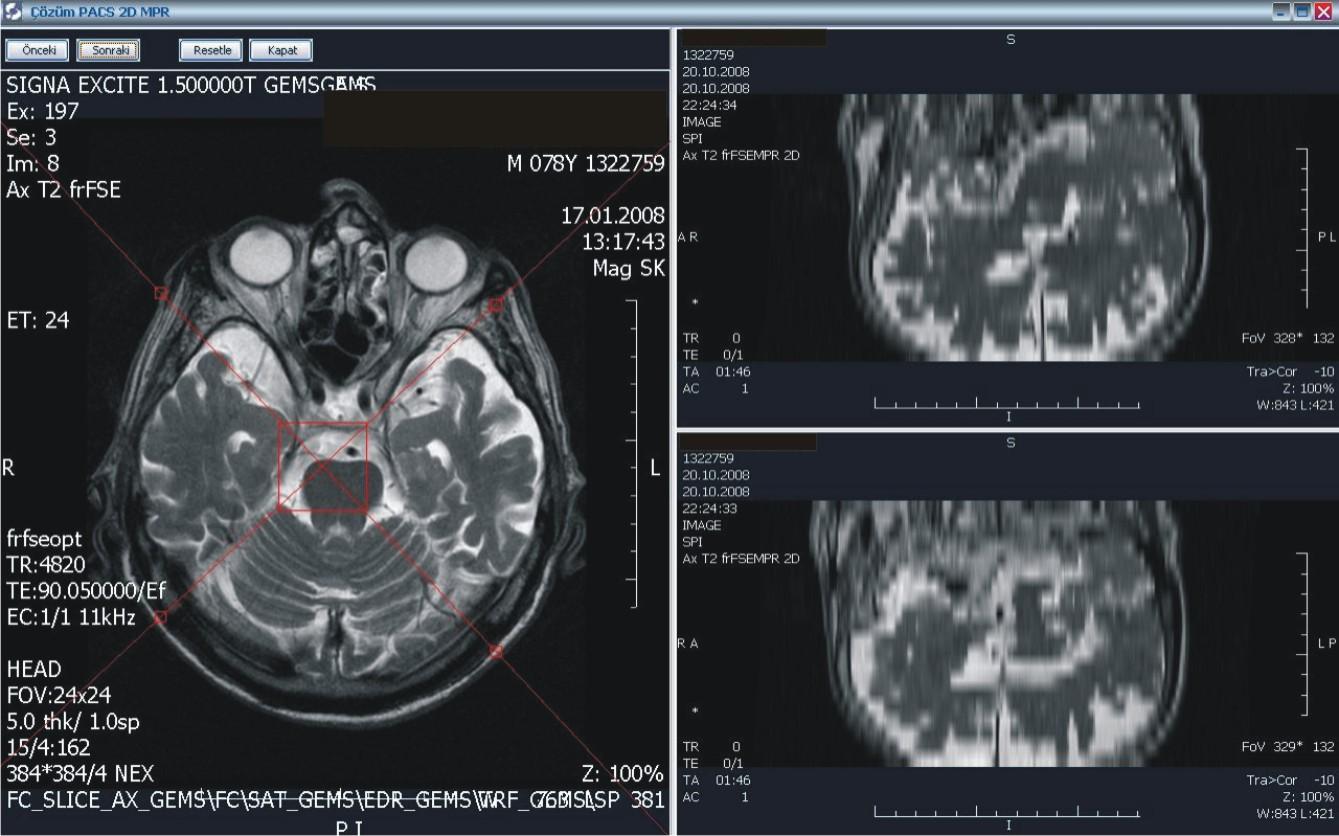

Hastanemizde bilgi yönetim sistemi olarak Çözüm HBYS'yi (Hastane Bilgi Yönetim Sistemi) kullanıyoruz. Güçlü bir entegrasyon sağlamak adına uluslararası standartlara haiz, tamamı Türk mühendislerine ait tek PACS olma özelliğindeki Çözüm PACS'ı tercih ettik.

PACS ile, dijital olarak elde edilen panoramik ve lokal radyolojik görüntüler (ultrasonografi, doppler, magnetik rezonans, tomografi v.b. cihazlardan elde edilen veriler) çevrimiçi ortamlarda dijital arşivleme yöntemleriyle saklanıyor. Kayıpsız bir şekilde, hızlı ve güven içinde saklanan bu görüntüler, gerektiğinde istemcide yeniden görüntülenerek kullanılabiliyor.

Merkezi veri tabanında bilgilerin depolanması ile oluşan dijital arşiv (görüntüler üzerinde işlem yapmaya izin verecek şekilde yüksek çözünürlükte saklandığı için ölçüm ve tanıya ilişkin işlemler kolaylıkla yapılabiliyor), bilgilerin yeniden kullanılmasını arşivlenen bilgilerin modern tanı yöntemleri ile incelenmesini sağlıyor. Dijital görüntüler üzerinde işlem ve ölçüm yapılabiliyor. Görüntüler ve raporların her an, her yerde (tüm iş istasyonları üzerinden sorgulama yapılarak) ulaşılabilir olmasına ve görüntü işleme ve ölçüm (mesafe, açı, uzunluk, yoğunluk) yapılabilmesine imkan sağlıyor.

PACS, tanı ve teşhislerde daha doğru sonuçlar elde edilmesini sağlayarak  sonuçları  yorumlama ve raporlama süresini hızlandırıyor. Görüntülerin karşılaştırılması ve radyolojik bulguların geriye dönük değerlendirilmesi, karşılaştırmalı raporların incelenmesi, hekimin hastalığın gelişim sürecini daha iyi kavramasını ve doğru teşhisi daha hızlı bir şekilde koyabilmesini sağlıyor. Yedeklenen PACS görüntüleri istenildiğinde hastalara CD-DVD halinde veriliyor.

Modern ve hızlı sistem sayesinde hasta ve sağlık çalışanlarının karşılaşabileceği radyasyon riski oranını azaltıyor. iş süreçlerini kısaltıp, hasta trafiğini azaltarak, medikal bölümlerin ve radyolojistlerin üretkenliklerini artırıyor.